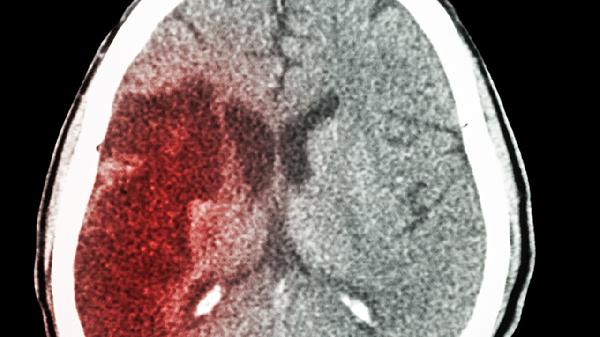

脑梗与睡觉有关?医生:上了年纪,睡觉一定要注意5点,别大意了

上了年纪的人总说"睡个好觉比吃补药还管用",可您知道吗?不恰当的睡眠方式可能悄悄埋下健康隐患。最近神经内科医生特别提醒:某些睡眠习惯与脑梗风险存在微妙关联。